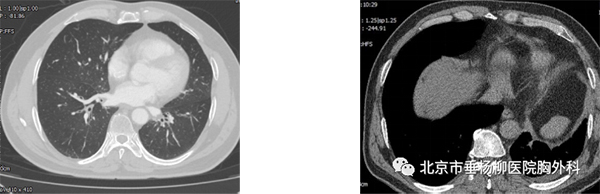

患者男性,60岁,主因“发现左肺下叶占位1月余。以“左肺下叶占位”入院,胸部增强CT:左肺下叶脊柱旁类圆形实性结节影,直径4.5*4.2cm,边界较清晰,增强扫描未见明显强化,可见腹主动脉分支血管进入病灶内。术中叶裂分化不全,左肺下叶与膈肌及纵膈胸膜粘连明显,遂行胸腔镜下左肺下叶切除术,手术历时4小时,完整切除肿物,术后病理回示:叶内型肺隔离症。术后患者恢复良好,术后5天拔出胸腔引流管,术后7天出院。

术后胸部CT(肺窗) 纵膈窗